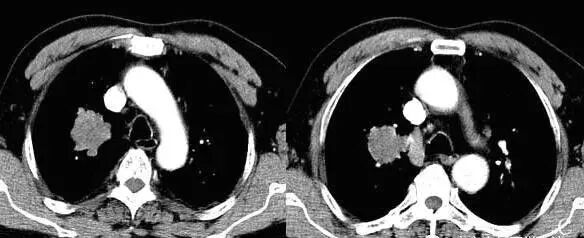

随着国内外医学影像检查的飞速发展,X光机、CT、MRI在临床工作中的广泛应用,医学影像诊断为精准医疗提供了坚实的基础,但基层医疗卫生单位医学影像工作人员的诊断水平急需提高。

(2)、X光片、CT、MRI及造影片的阅读法。

(3)、脊柱影像检查基础方法介绍和X光片判读技术。

(4)、根据影像检查结果如何判断定位脊柱相关疾病。

(5)、颈、胸、腰、骶椎,骨盆及骶髂关节的观片技巧及典型病例解析、答疑)。